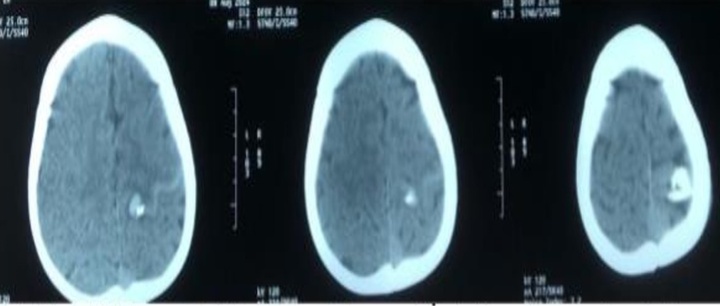

Vnexpress dẫn lời bác sĩ Nguyễn Đức Thế, Phó trưởng Khoa Chấn thương, Chỉnh hình, Bỏng cho biết bàn tay trái dập nát rất nặng, không có khả năng bảo tồn, phải cắt cụt, sau đó ê kíp xử lý các vết thương ở vùng mặt, mắt, hai cẳng đùi. Hiện bệnh nhân tỉnh, tiếp tục theo dõi, điều trị tại khoa.

Các bác sĩ xác định bệnh nhân bị chấn thương dập nát bàn tay phải, xử trí băng ép cầm máu, giảm đau, chống sốc, kháng sinh, chuyển bệnh nhân vào phòng mổ xử trí. Hiện sức khỏe của nạn nhân đã tạm thời ổn định.